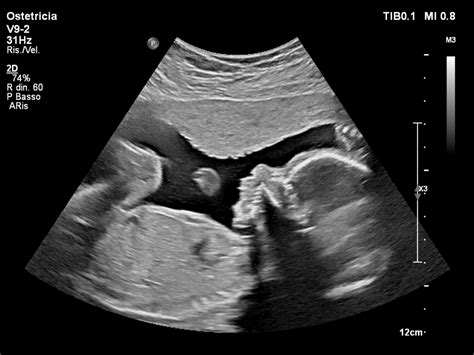

La Diagnostica Prenatale: Strumento Essenziale per la Sicurezza

Per quanto riguarda la diagnostica prenatale, gli esami raccomandati hanno ormai ridotto il rischio di morte sia della madre che del bambino. I genitori possono inoltre conoscere in anticipo l’eventualità di anomalie cromosomiche, escludere difetti congeniti o malformazioni, garantendo una maggiore tranquillità e la possibilità di prepararsi a eventuali sfide.

- Amniocentesi: Attraverso l’amniocentesi, il liquido amniotico viene estratto dall’interno della placenta, la sacca in cui si trova il feto. La puntura viene eseguita con un ago sottilissimo attraverso l’addome e dall’embrione vengono prelevate cellule che verranno analizzate per individuare l’eventuale presenza di anomalie cromosomiche o genetiche e difetti del tubo neuronale. Si svolge tra la 15ª e la 18ª settimana di gestazione.